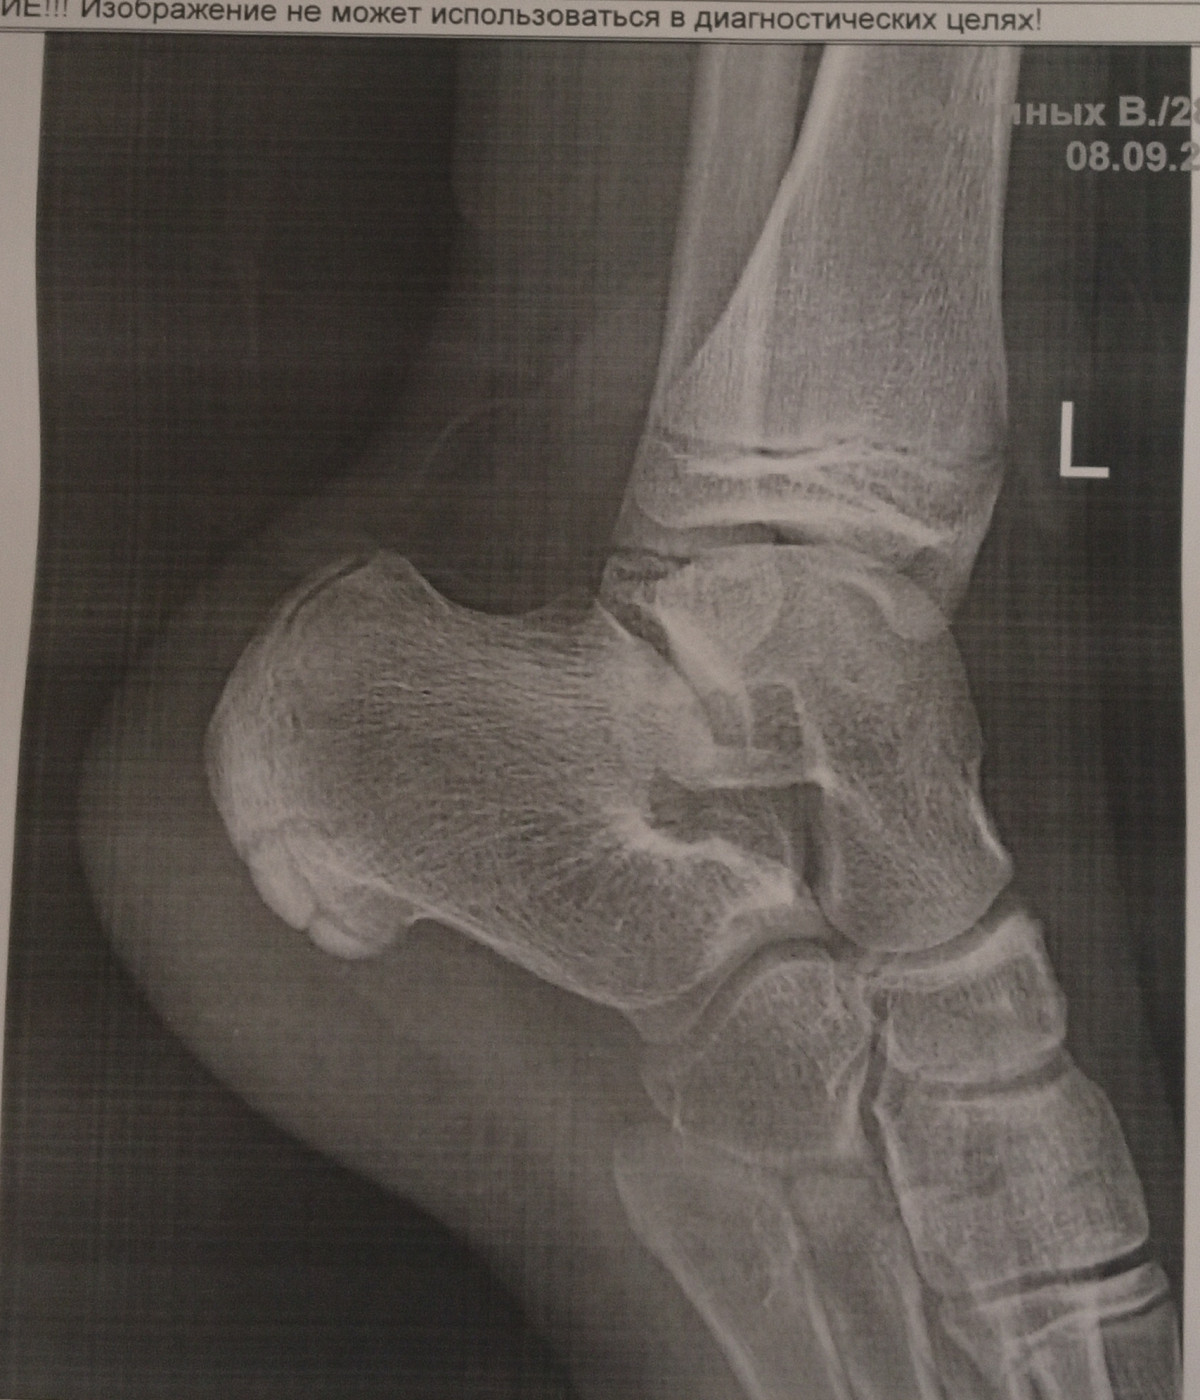

Есть ли перелом со смещением

Подвернула ногу